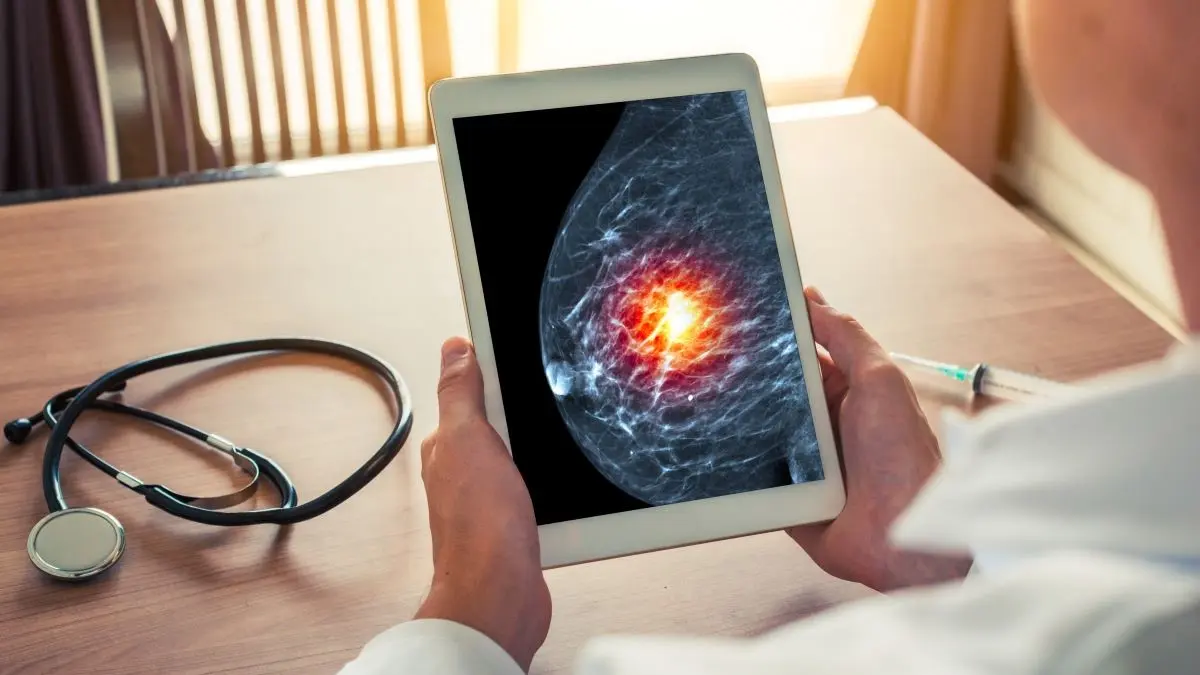

Therapie bei triple-negativem Brustkrebs im Fokus

Brustkrebs-Operation mit KI-Unterstützung

🔒 Giredestrant bei fortgeschrittenem HR+/HER2- Brustkrebs